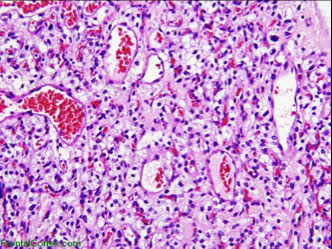

HUS